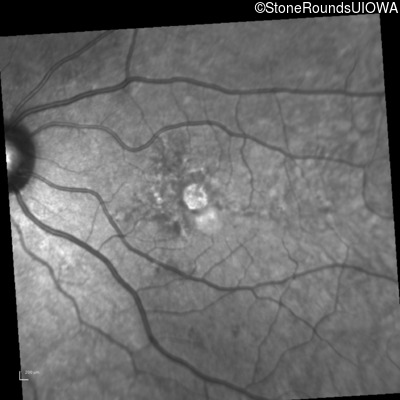

Infrared Fundus Photograph - Right - 20/20 +1

Exemplar